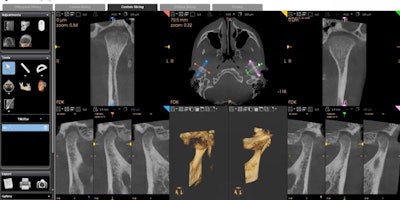

Sometimes, the patient just needs a crown repaired -- and Dr. David Rice, clinical editor for DrBicuspid.com, has already shared how to safely and quickly treat patients -- but sometimes 3D imaging could reveal more. The affordability, ease-of-use, and compact size of today's multimodality CBCT systems, like a CS 8100 3D Evo Edition or CS 8200 3D (Carestream Dental), mean more general practitioners (GPs) are wanting to dig deeper with 3D on tricky cases.

A low-dose 3D scan can be beneficial for evaluating the temporomandibular joint (TMJ), which is often affected by clenching and grinding, by providing a clear image of the condyles. With CBCT, a doctor can assess the volume and position of the condyle, determine the presence of asymmetry between right and left, evaluate the relationship between condyle and mandibular fossa, and detect changes that might suggest degenerative disease such as flattening, sclerosis, osteophyte formation, and erosion.

Fractures are typically caused by bone loss patterns around the root, meaning there's usually much more at play than what we can see during a clinical exam. When compared to a bitewing or panoramic, a 3D scan is significantly more successful at visualizing fractures, especially when combined with a focused field-of-view.